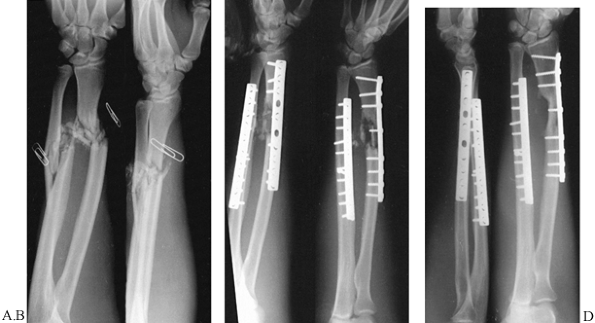

![]() |

Figure 16.10. Comminuted intraarticular supracondylar fracture of the humerus with double plate fixation. A:

AP radiograph showing extreme comminution of the distal humerus in a 17-year-old girl who fell off a horse. The medial and lateral columns are fractured. There is comminution around the olecranon fossa. The junction between the trochlea and the capitellum is comminuted, with the majority of the trochlear notch consisting of two completely free fragments. B: Lateral radiograph showing the comminution with complete anterior displacement of the capitellum, which is dislocated free from the radial head. C: Postoperative AP radiograph showing reconstruction of the articular components with a lateral to medial lag screw. The two K-wires provide additional fixation for the free fragments. The integrity of the medial and lateral columns has been restored with 3.7 titanium Alta (Howmedica, Rutherford, NJ) reconstruction plates. The fracture is anatomic. D: Lateral radiograph of the fixation showing anatomic reduction. It was possible to start immediate motion in this elbow. At 6 months follow-up, the fracture had healed and the patient’s range of motion was from 10° to 135° of flexion, with full supination and pronation. Note that this was done with a comprehensive posterior triceps-splitting approach, and olecranon osteotomy was not necessary. |